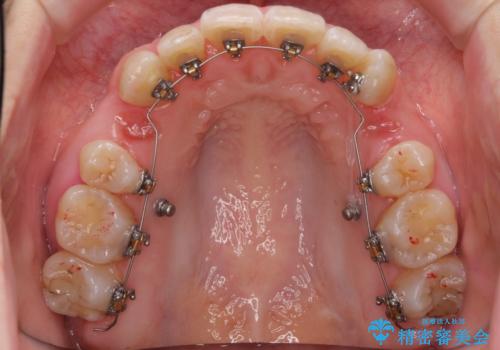

- 矯正装置

- ハーフリンガル

矯正治療で右下を抜歯し、スペースを天然の歯でつめる矯正治療を行いました。

上顎前歯も唇側傾斜しておらず、もともと叢生が多くない状態で上下左右を抜歯した上、リンガルで治療を行なったため、多少治療期間がかかりました。